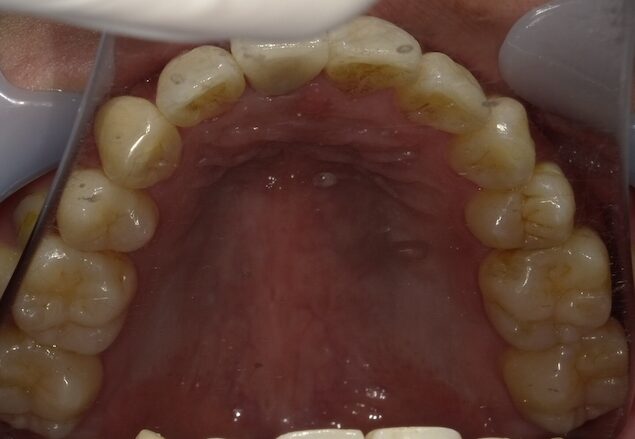

症例③:2回の矯正経験者

前歯の上下的なズレに対しワイヤー矯正で対応。

治療後は裏側ワイヤー固定+夜間リテーナーで安定。

治療方法 ワイヤー部分矯正/治療期間 8ヶ月/治療費用¥440000(税込)

治療のリスク デメリット 裏側でのワイヤー固定を長期的にする必要がある